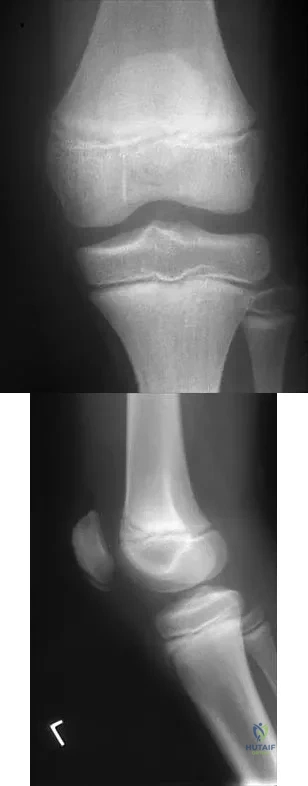

Question 66

Figure 24 shows the radiograph of a 10-year-old boy who sustained a valgus injury to the knee. Examination reveals grade III medial laxity. Initial management should consist of

Question 79

Figures 10a and 10b show the radiographs of an athletic 9-year-old boy who has activity-related anterior knee pain with intact active knee extension. Examination reveals tenderness to palpation over the inferior pole of the patella. There is no effusion or ligamentous instability. Initial management should consist of